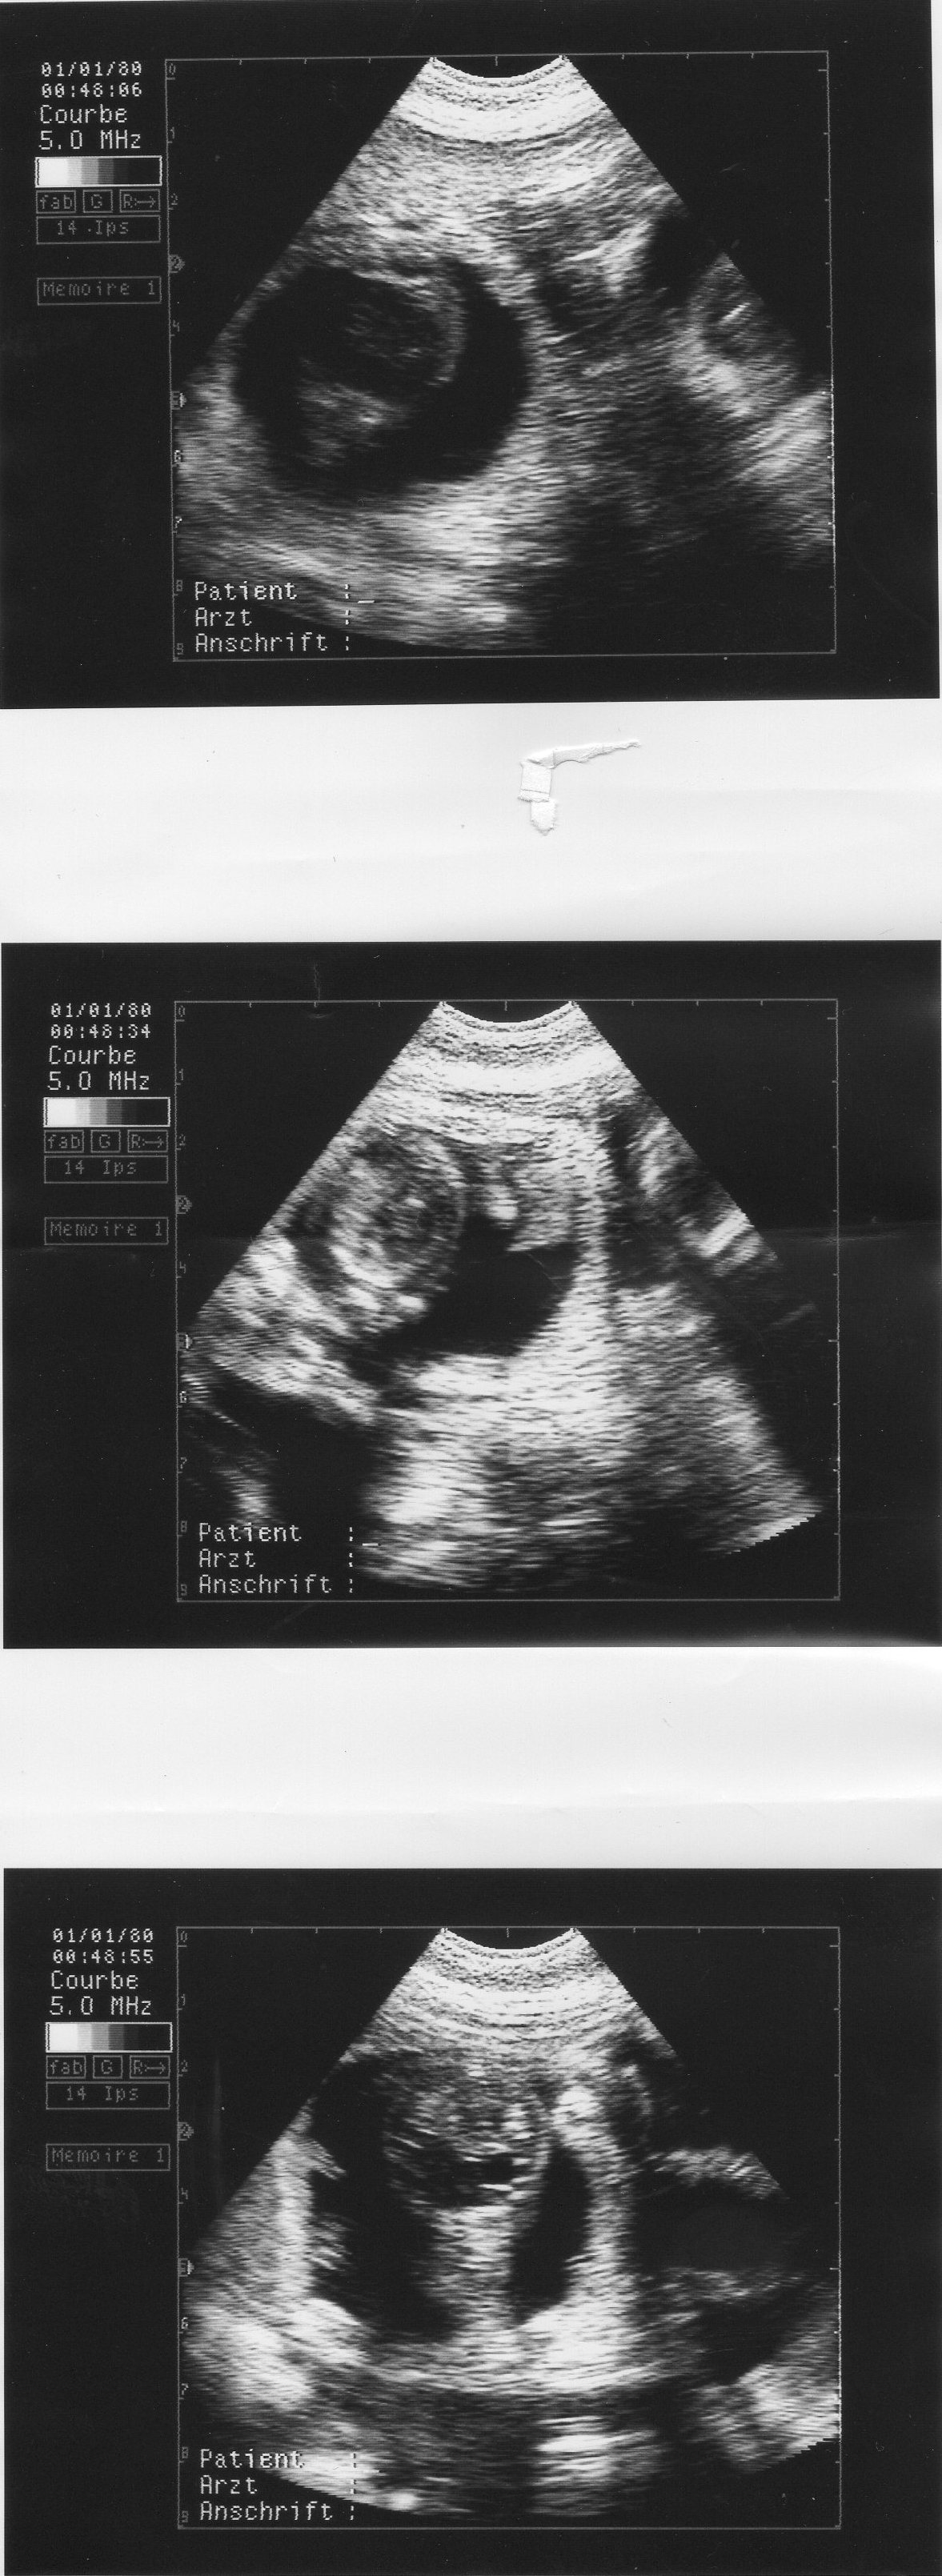

Heute am frühen abend bekamen wir das positive Ultraschall Ergebnis

Chimbazi ist schwanger

Heute am 05.11.2009 haben wir Chimbazi zum zweiten Mal schallen lassen

Die Tierärztin ist mit Chimbazi und den kleinen Fruchtwasserschwimmern zufrieden

hier die Fotos